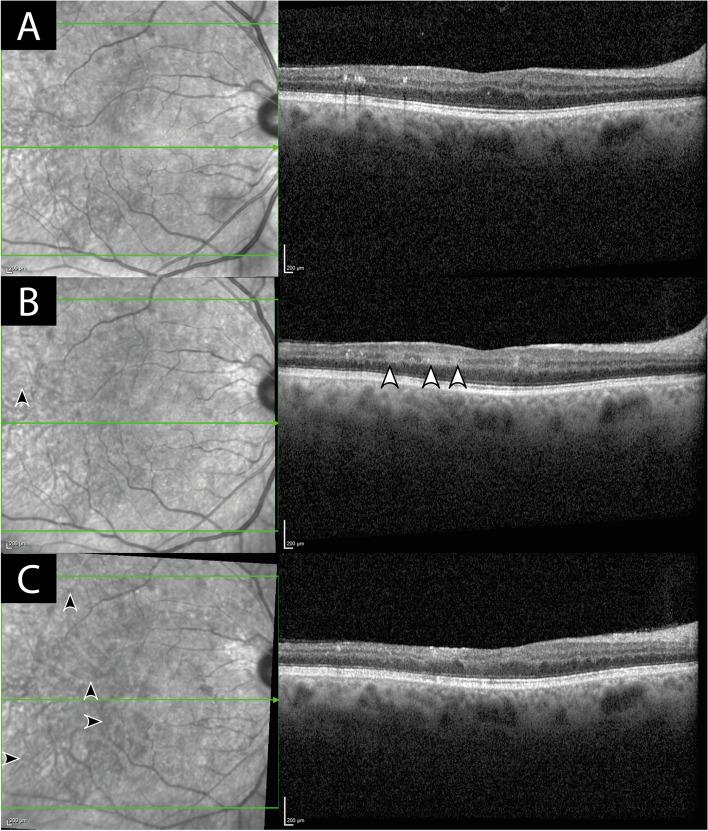

A 52-year old man treated with monthly Faricimab injections for diabetic macula oedema presented with sudden reduced vision, new retinal hemorrhages, significant retinal vascular occlusions and ischemia. After screening for differential diagnoses was unremarkable, the patient was treated with oral and intravitreal steroid therapy under which the occlusive vasculitis was stabilized.

一名52岁男性因糖尿病性黄斑水肿接受每月一次的法西单抗注射治疗,出现视力突然下降、新的视网膜出血、显著的视网膜血管闭塞和缺血。在排除鉴别诊断无异常后,该患者接受了口服和玻璃体内类固醇治疗,在此治疗下闭塞性血管炎病情稳定。